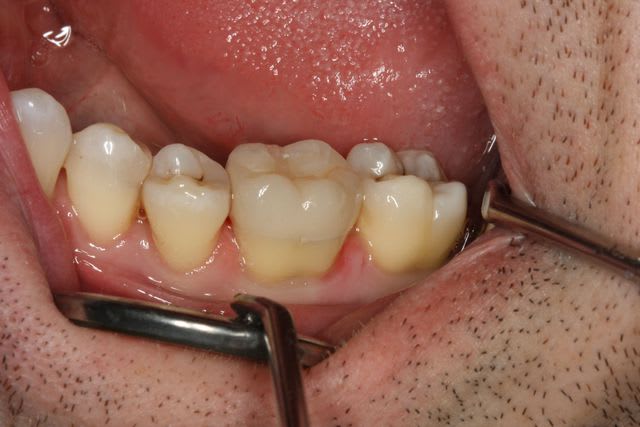

Un petit onlay du dimanche dernier qui m'a fait plaisir. A souligner le travail du prothésiste, content de son boulot après avoir vu les photos.

Pour Sethef: la digue (medium) ne m'a pas gêné, mais le premier clamp que j'ai voulu mettre remontait partiellement sur la limite.

Petite question, par curiosité: la cavité a l'air profonde sous la gencive, non?

La cavité d'accès pour une dévit est insuffisante , la dent est vivante . La limite de la cavité est sus gingivale .

Dent vitale. Il y avait un compo OD et le pan V a lâcher. Limite supra-gingivale.

Ci joint une autre vue.